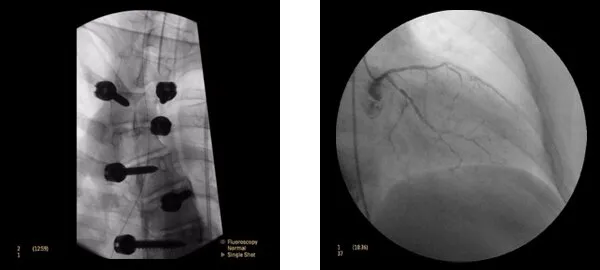

Клинические изображения

Philips Veradius Unity может полноценно работать как в отделениях ортопедии, электрофизиологии, онкологических отделениях при проведении биопсии, дренирования, нейролизиса, так и в отделениях, занимающихся диагностикой и лечением сосудистых заболеваний, включая кардиологические

Philips Veradius может полноценно работать как в отделениях ортопедии, так и в отделениях электрофизиологии, онкологических отделениях при проведении биопсии, дренирования, нейролизиса. В отделениях занимающихся диагностикой и лечением сосудистых заболеваний, включая кардиологические.​

Новый динамический плоский детектор 27×27 см позволяет получать изображение с гораздо более качественным изображением по сравнению с традиционными усилителями изображения.

• Набор программ для нейрохирургии, исследований сердца и сосудов.